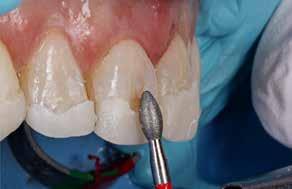

I samråd med patienten og egen tandlæge* afstemmes forventningerne, inden der bestilles refinement alignere. Nivelleringen af alle tænder i tandbuerne, smilelinje og -kurve samt den bukko-lingvale position af incisiverne foretages og efterfølges af retainers lingvalt på over- og underkæbeincisiver (Fig. 3 A-D). Hele behandlingen udføres under løbende kommunikation med patient og egen tandlæge*, der udfører den efterfølgende rekonstruktion med direkte plast (Fig. 4 A-D). Behandlingsvarigheden har været to år og to måneder, hvor ortodontien har forløbet over 21 måneder. Der har været anvendt et første sæt på 66 alignere samt yderligere to sæt med ni refinement alignere. Tandblegning og direkte plastrekonstruktion er udført af egen tandlæge* (Fig. 5 A-F).

Fig. 5. A, B. Smil og kæbeforhold før og efter. Et bredere smil med korrektion af de laterale mørke rum. C-F. Harmonisk hældning af overkæbe- og underkæbeincisiver, rekonstruktion af den tabte tandsubstans efter nivellering af gingivaniveau og optimal bukko-lingval placering til direkte plastbehandling.

5. A, B. Smile and jaw relationships before and after. A wider smile with correction of the lateral dark spaces. C-F. Harmonious inclination of the upper and lower jaw incisors, reconstruction of the lost tooth substance after leveling the gingival level, and optimal bucco-lingual positioning for direct plastic treatment.